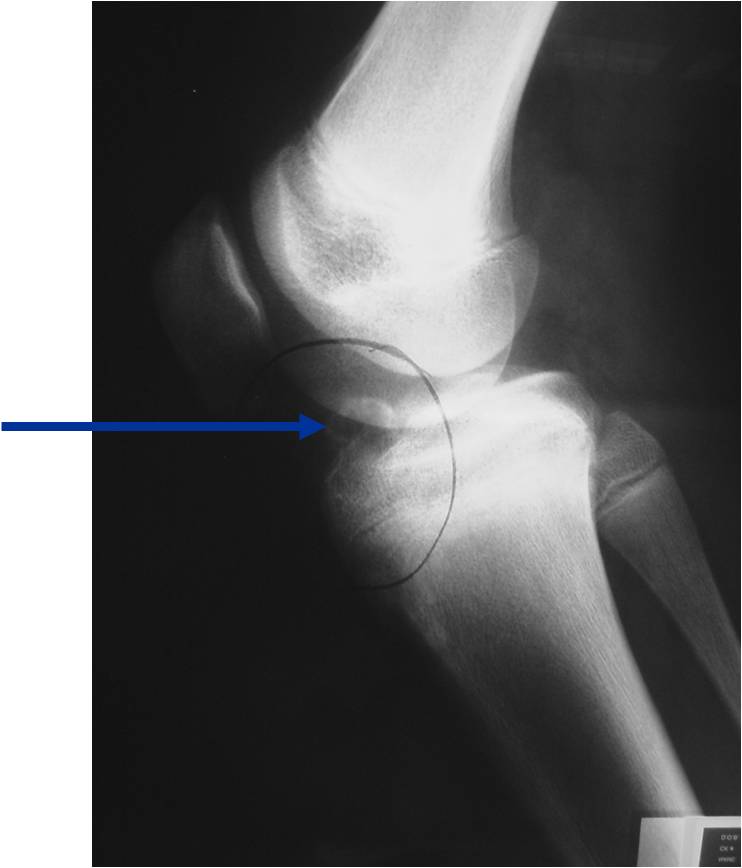

Radiographic Presentation

- Presents as a highly defined/well circumscribed geographic oval/round lytic defect

- Surrounded by rim of sclerotic bone

- Usually in epiphyseal region

Plain x-ray appearance:

- Geographic lytic lesion IA/IB margin of sclerosis

- Usually Eccentric more often than Central in the bone

- Rarely expansile (rarely penetrates the cortex)

- Calcified chondroid matrix 30%-50% of cases

- Often better detected with a CT Scan

- Periosteal Reaction 30-50% of cases

- Usually occurs in Adjacent Diaphysis/Metaphysis since epiphysis is intraarticular and not surrounded by periosteum